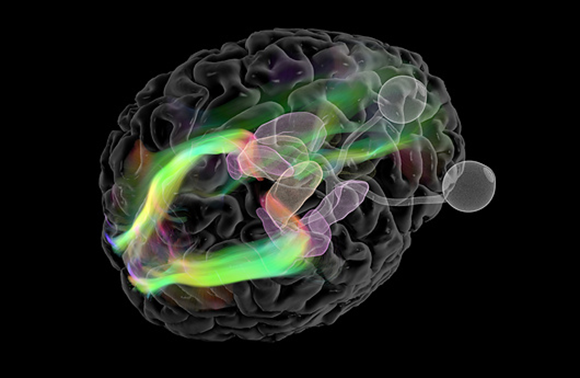

يتعيّن على عدد كبير جدًّا من الخلايا أن تعمل على إجراء المعالجة الأساسيّة لجميع المعلومات التي يستقبلها أذهاننا من العالم الخارجيّ. صورة بالرنين المغناطيسيّ للممرّات العصبيّة من العين إلى القشرة البصريّة في الدماغ | المصدر: Mark And Mary Stevens Neuroimaging And Informatics Institute / Science Photo Library